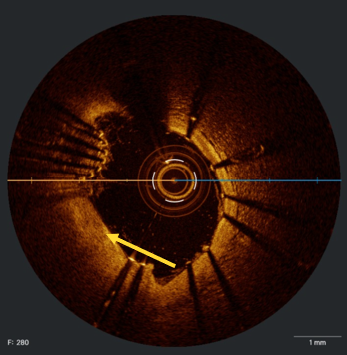

In view of this complication and the clinical instability of the patient, extraction of the device with a coronary snare was attempted but was unsuccessful (Figure 3). The access route was then changed to the femoral artery using an Amplatz left 6F catheter, and a Sion guidewire was advanced to the distal segment of the right coronary artery with the support of a 135-cm FineCross microcatheter (Terumo). This was followed by dilatation using a Sapphire II PRO balloon (OrbusNeich) (Figure 4) with catheter extension and anchoring of the balloon until 2 new everolimus-eluting stents (2.5 x 40 mm and 3.0 x 15 mm) could be advanced (Figure 5). Upon post-dilation of the noncompliant balloon, the previous stent and ballon were successfully crushed, obtaining a good final angiographic result (Figure 6). The procedure was completed with intracoronary optical coherence tomography, which confirmed adequate stent expansion and apposition, as well as the crushing of both the stent and the previous balloon (Figures 7-11).